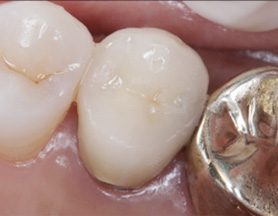

염증을 제거하는 신경치료 후 치근단 부위가 빠르게 회복되어 깔끔하게 신경치료를 완료하고 크라운 보철물을 씌웠습니다.

신경치료를 받은 치아는 약해져 있기 때문에 크라운 보철물로 씌워주어 세균 감염을 예방해야 합니다.

신경치료를 받은 치아는 수분이나 영양공급이 이루어지지 않기 때문에 쉽게 치아가 부서지거나 깨질 수 있으므로,반드시 신경치료 한

치아는 크라운을 씌워 치아를 보호해 주어야 합니다.